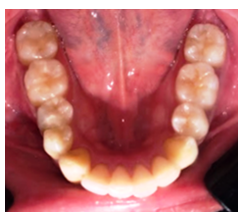

Se presenta el caso clínico de paciente masculino de 27 años de edad que acudió al postgrado de cirugía bucal de la Universidad Latinoamericana y del Caribe con sede en Instituto docente López Arévalo de la ciudad de Valencia (Edo. Carabobo, R.B. Venezuela), sin antecedentes personales ni familiares contributorios, que asistió a consulta asintomático, refiriendo secreción blanco-amarillenta en mucosa de trígono retromolar inferior izquierdo, desde julio de 2021 sin tratamiento previo. En el examen clínico no se evidencia aumento de volumen ni asimetría facial, paciente niega fiebre, tumefacción y dolor en la zona (Figura 1).

Figura 1 Imagen Oclusal inferior que evidencia simetría de las corticales vestibulares y linguales de ambas hemiarcadas. Fuente: Historia Clínica. Especialización Cirugía Bucal ULAC-IDOLA. 2022.